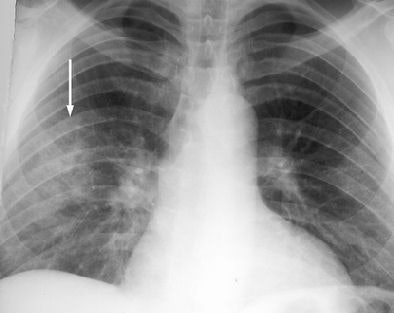

These are your lungs on crack

On x-rays, acute lung injury after cocaine use can appear as "bilateral, perihilar areas of increased opacity or attenuation, usually without pleural effusion or cardiomegaly," according to Dr. Michael Gotway and colleagues from San Francisco General Hospital; the University of California, San Francisco; and Brigham and Women's Hospital in Boston. "High-resolution CT may show multifocal ground-glass attenuation associated with septal thickening," but the condition clears up quickly after discontinuing cocaine use, they reported (RadioGraphics, October 2002, Vol. 22:4, pp. S119-S135).

| Acute lung injury (crack lung) in a 37-year-old man who presented with shortness of breath and cough after crack use. Above, frontal chest radiograph reveals ground-glass areas of increased opacity in the right lower lobe (arrow), a finding that is consistent with numerous causes, including edema, infection, hemorrhage, and aspiration. Below, high-resolution CT scan (level = -700 HU, window width = 1,000 HU) reveals ground-glass attenuation (arrows) with interlobular septal thickening (arrowheads). The differential diagnosis of these findings includes infection (especially Pneumocystis carinii pneumonia), lipoid pneumonia, and alveolar proteinosis, among numerous other causes. Bottom, frontal chest radiograph obtained two days after CT shows resolution of the increased opacity. Fig. 3a, b, c. Gotway MB, Marder SR, Hanks DK, et al. "Thoracic Complications of Illicit Drug Use: An Organ System Approach." RadioGraphics. 2002;222:S119-S135. |